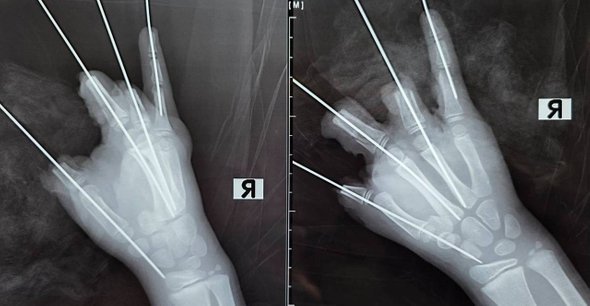

Врачи Санкт-Петербургского педиатрического медицинского университета провели пятичасовую операцию мальчику из Ленобласти, у которого в руке взорвалась петарда. Как сообщает тг-канал СПбГПМУ, хирурги боролись «за каждый сантиметр тканей», однако ребенку пришлось ампутировать четыре пальца. У пациента также сильно поврежден мизинец и диагностированы открытый перелом и вывих пясти.

Инцидент произошел в Приозерском районе Ленобласти. Во время прогулки у восьмилетнего мальчика в руке взорвалась петарда, которую ему предположительно продали в продуктовом магазине. Скорая доставила пациента в клинику Педиатрического университета и мальчику провели экстренную операцию, которая длилась пять часов.

«Мы постарались сохранить максимально возможный объем тканей. К сожалению, повреждения были очень серьезными, многие мягкие ткани были утрачены. При такой травме реконструировать конечность не представлялось возможным. Мы боремся за каждый сантиметр тканей, который можно сохранить. Разрыв даже небольшой петарды, зажатой в кулаке, может приводить к травматической ампутации пальцев. Более того, в нашей практике были случаи травматической ампутации всей кисти в подобных ситуациях», — рассказали хирурги,

Сейчас школьник остается в реанимации. Врачи отмечают, что в ближайшие несколько дней возможна некротизация некоторого объема тканей кисти, что характерно для подобных травм.